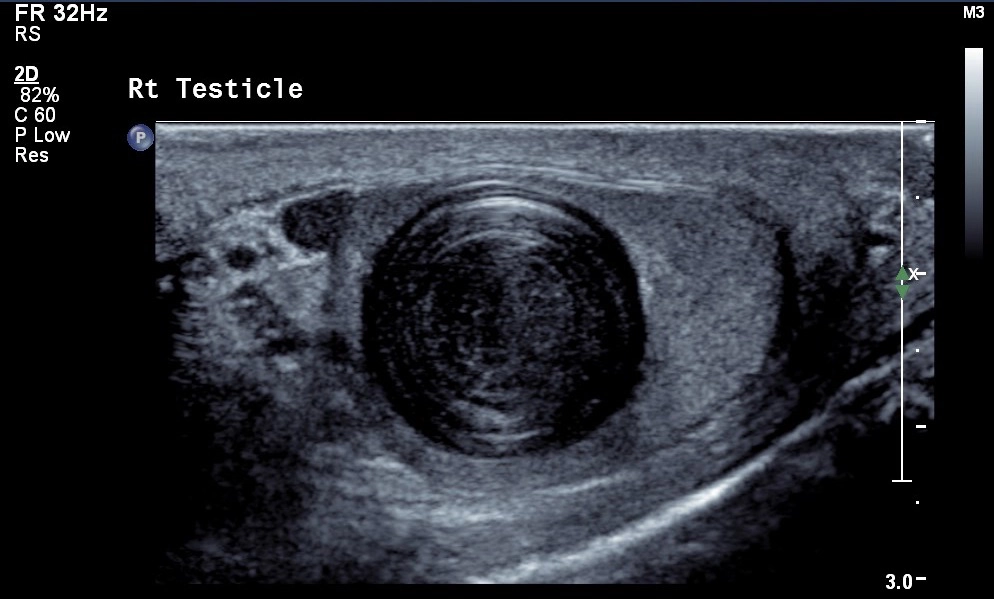

• Khối u tinh hoàn

Nang thượng bì tinh hoàn (Testicular epidermoid cyst)

Di tích thượng thận tại tinh hoàn (Testicular adrenal rests- TART)